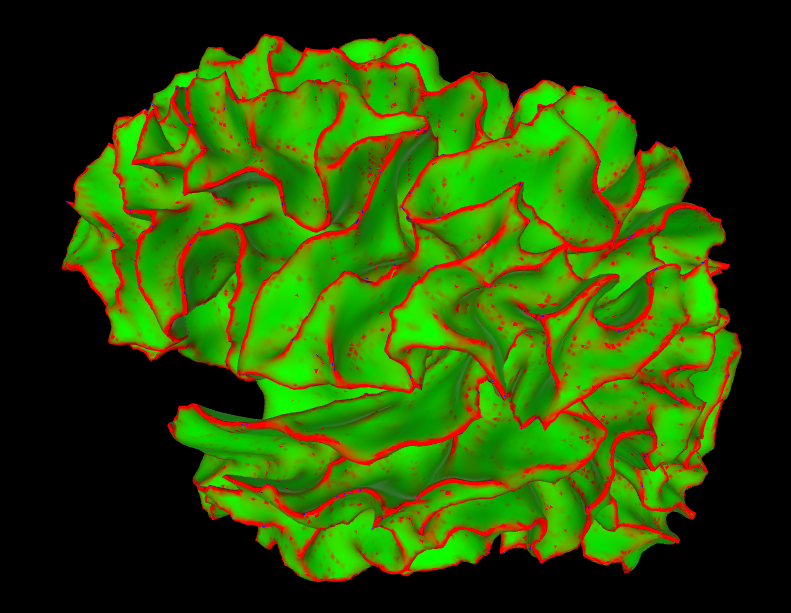

Marching Cubes creates 3D Meshes

Bill Lorensen 1987